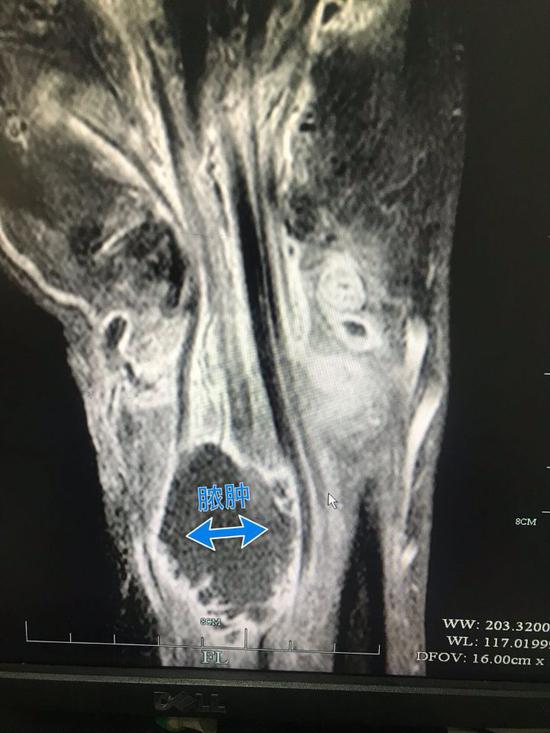

半年之后,姚先生找到了杭州的一家醫院,檢查顯示姚先生的右手腕持續流膿,伴隨著惡臭和疼痛,CT片顯示膿腫肌腱斷裂,醫生告訴姚先生,這種情況可能要截肢……